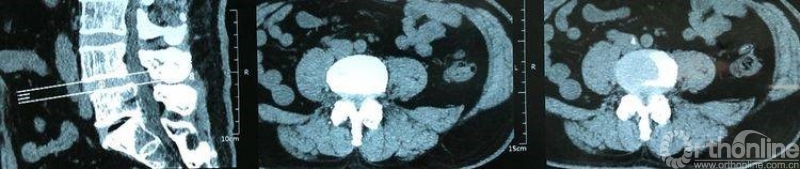

术前CT示L4/5重度椎管狭窄,腰椎滑脱合并硬膜囊受压。辅助检查如下:

术前CT